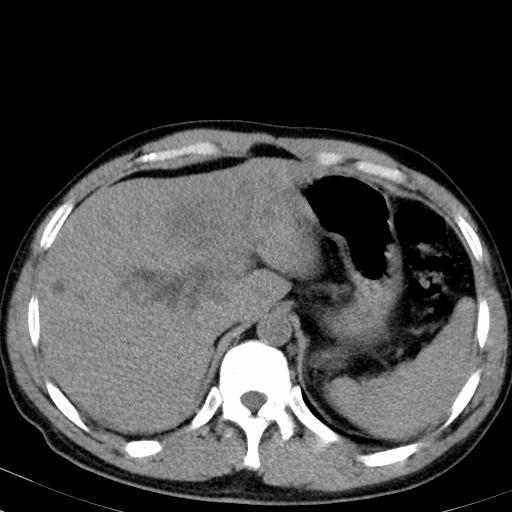

患者上腹部疼痛一月余,伴巩膜黄染;

实事求是的说,强化效果很一般,重点部位应重点观察,但有一点可以明确:肝门部胆管细胞癌。

考虑肝左叶胆管细胞癌侵犯肝门区并肝内胆管及肝总管扩张。

肝左叶肿块清度增强,所在的叶胆管扩张。考虑胆管细胞癌。

考虑肝左叶胆管细胞癌侵犯肝门区并肝内胆管及肝总管扩张、肝门淋巴结肿大。